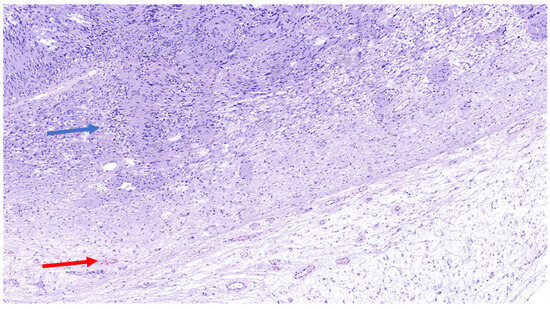

The schwannoma–neurofibroma hybrid is one of the more commonly described HPNST variants and is frequently associated with NF1- and NF2-related schwannomatosis, as well as other forms of schwannomatosis. Although accurate diagnostic criteria have not yet been established [6], these tumors exhibit distinct cellular components: Schwann-cell nodules exhibiting Antoni A areas with nuclear palisading and Verocay bodies, and strong immunoreactivity for SOX10 and S100, while intermixed neurofibroma-like regions consist of elongated, wavy nuclei, fibroblasts, and a collagen-rich myxoid matrix, often organized in a plexiform arrangement (Figure 5), with scattered S100/SOX10 staining, and entrapped NFP-positive axons. As mentioned above, immunohistochemically, schwannomatous areas are strongly positive for S100 and SOX10, whereas the neurofibroma component expresses S100, SOX10, CD34, EMA, and GLUT-1 (Figure 6). These tumors are usually slow-growing and asymptomatic, and they have a low recurrence rate following surgical excision. However, when associated with NF1, there is a potential risk of malignant transformation into MPNSTs [7].

Figure 5. H&E (100× magnification) of a peripheral nerve sheath tumor with features of schwannoma and neurofibroma. The schwannomatous component: elongated cellular bundles, Verocay bodies (blue arrow), and an Antoni A/B pattern. The neurofibromatous component: heterogeneous cellular population, scattered spindle cells within a more myxoid matrix (red arrow).